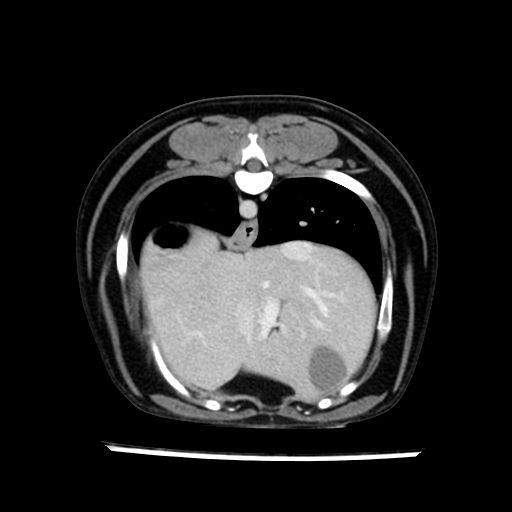

prescritto esame TAC

sequenza immagini limitata al fegato reni e surreni

le immagini ecografiche rispetto alla tac datano circa 7 mesi prima ,le surrenali sono normali nonostante il test acth sia risultato positivo .all’esame TAC dopo diversi mesi risultano aumentate armonicamente nel volume e si individua un forte sospetto di adenoma ipofisario .

sospetto adenoma ipofisario vs. meno probabilmente meningioma della base; intertiziopatia polmonare; lesione espansiva epatica, verosimilmente del lobo laterale sinistro, di sospetta natura neoplastica; lesioni spleniche di natura da definire; iperplasia/ipertrofia delle ghiandole surrenali, bilateralmente; vertebra di transizione del rachide toracico; tenosinovite cronica del muscolo bicipite brachiale di destra.

- Nessuna informazione diversa per quello che riguarda l’esame ecografico del fegato e la presa del contrasto si confermano le lesioni individuate e l’ipoenanchement in fase portale.